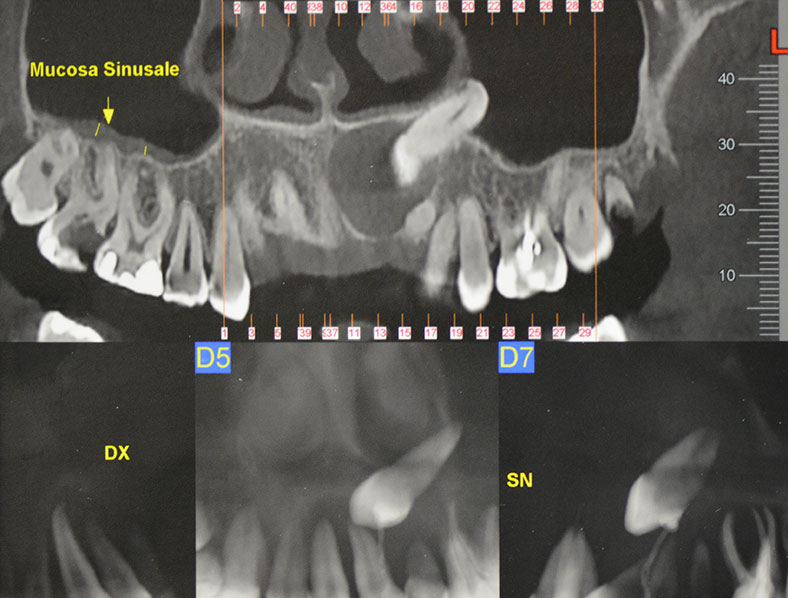

In questa immagine radiografica è presente l’inclusione di un canino superiore con annessa cisti follicolare.